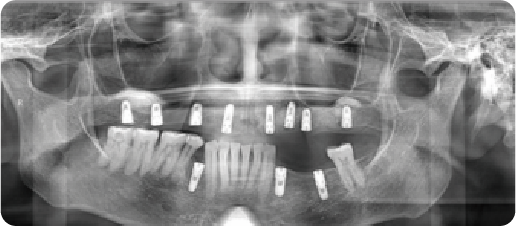

A case of generalized mobility in the remaining teeth and complete edentulism.

Name:Mr PanAge:62

Evaluation: Wearing a removable denture over the long term can loosen and eventually cause the loss of your natural teeth, which can significantly diminish your appetite.

Treatment Plan: The treatment involved extraction of the residual mobile teeth and immediate placement of 12 implants with a fixed prosthesis.

Patient Feedback: It feels solid—I can bite with confidence. My healthy teeth were left alone, and they look so natural and feel so comfortable, it's just like having my own teeth back